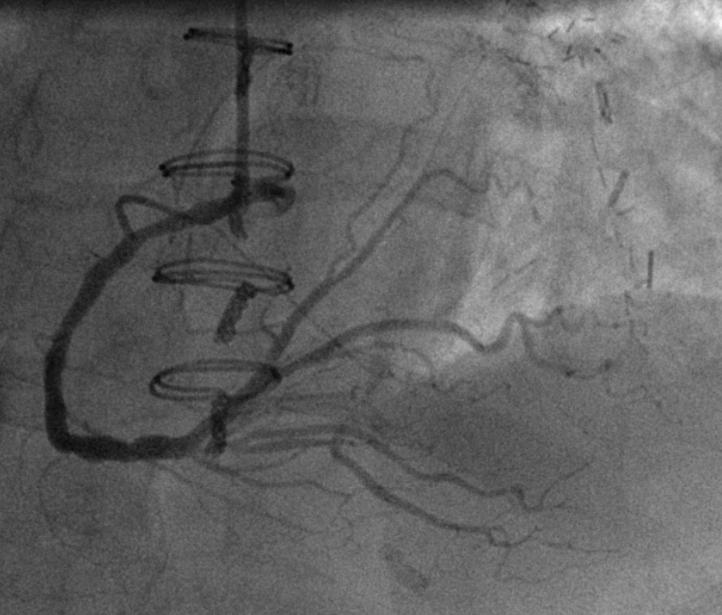

冠脉造影及桥血管造影图像

PLA经静脉桥血管向LCX提供少量侧枝循环

术中反复寻找造影,左主干及静脉桥血管开口闭塞

LIMA桥通畅,LAD远段TIMI血流3级,中段逆向血流显影可